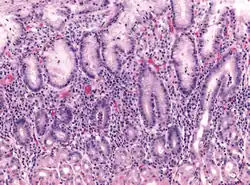

Micrograph showing gastritis. H&E stain.

Early acute superficial gastritis: Marked neutrophilic infiltrates appear in the mucous neck region and lamina with a pit microabscess. This case was caused by Helicobacter pylori.